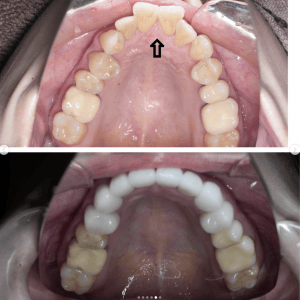

Case022 – インプラント

広島からの患者様です。

前歯を綺麗にしたい。インプラントをしたい。

という主訴で東京の歯医者をいろいろ調べて当院を選んでくださいました。

毎回、遠い中しっかり通ってくださり、選んで頂けた嬉しさと、その気持ちに応えたいという想いで診療させて頂きました。

前歯はご希望のお色でラミネートベニアでは出せない透明感のあるセラミックに上下左側7はインプラントをさせて頂きました。

左上は破折で温存不可。

骨も少なかったので、サイナスリフトも行い計五回の来院で被せ物を入れさせて頂きました。

左下は前回のクリニックでの埋入位置が深すぎて食べカスも毎回詰まる、セルフメンテナンスではら汚れも取れない。インプラント周囲炎にもなっていたので、一度前のインプラントを除去し、そこから新しくインプラントを埋入し、診療させて頂きました。

インプラント、歯並び、審美歯科にご興味のある方はいつでも相談にお越しください。

担当 理事長 佐藤 悠野